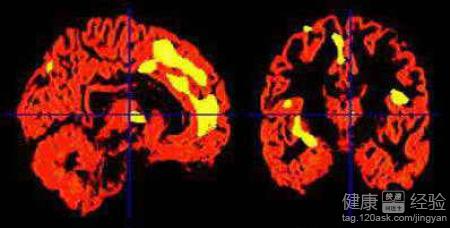

兒童多動症是指兒童的行為有點異常,可以理解為注意力缺陷的多動症或者是腦功能輕微的失調綜合症,在早產兒和剖宮產的孩子很常見。孩子的智商是正常的,但是學習、情緒和行為上有所缺陷。多動症的表現:注意力不集中、活動活躍、情緒激動、情緒沖動、人際交往差、學習差等等。引起小兒多動症的原因:遺傳因素、神經生理學因素、輕微腦損傷、神經生化因素、神經解剖學因素、心理社會因素等等。那麼臨床上有什麼好的方法治療呢?

2【復合療法】目前比較新穎的治療方法,稱為神經靶向修復療法。技術要求非常高,通過激活休眠的神經細胞,促使神經細胞的更新,可以代替損傷或者是死亡的細胞,促進器官的再次發育。